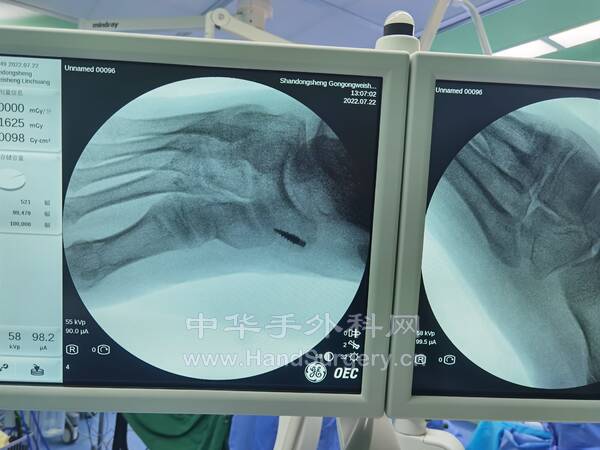

2.马蹄内翻足矫正术:

术式:跟腱延长术,跖筋膜松解术,胫前肌腱部分转位术(术中发现第三腓骨肌过细,(见图),以5.0mm铆钉固定于楔骨,编织固定胫前肌腱),跟骨截骨外移内固定术,第一跖骨上抬固定术,环形外固定架固定术

今天近距离看了环形外固定架,固定顺序,将固定好的三环置于小腿和足正中,2.5mm克氏针自腓骨中下段贯穿打入,垂直于胫骨打入4.5mm半针,上螺丝固定好中环,上环亦打入2.5mm克氏针1枚, 垂直于腓骨前内侧面打入4.5mm半针1枚,同法垂直于腓骨前外侧面打入4.5mm半针1枚,上螺丝固定好上环,

自第五跖骨远1/3外侧和第一跖骨远1/3内侧。各斜行打入2.5mm克氏针1枚,自跟骨后侧交叉打入4.0mm半针固定,用螺丝固定好下环,最后上连接杆,调整外固定架的角度!